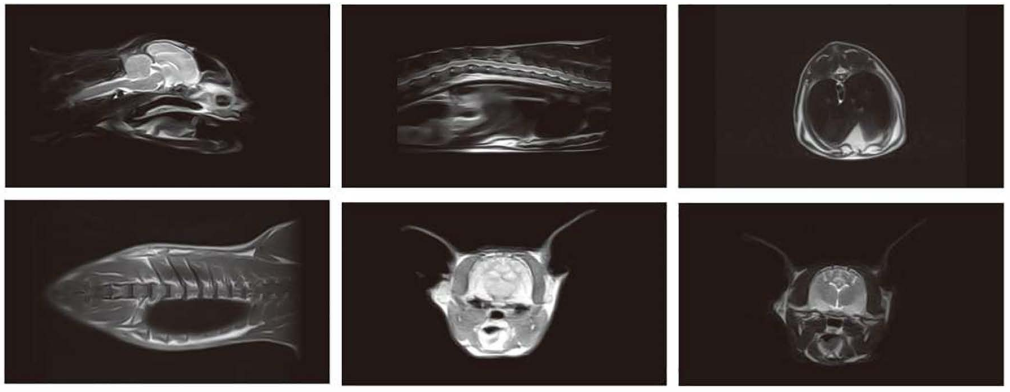

Độ phân giải cao, chụp toàn thân từ đầu đến chân

Chẩn đoán hình ảnh trong thú y: chụp sọ não, cột sống, khớp, ổ bụng, vùng chậu

Hỗ trợ điều trị và theo dõi các bệnh lý thần kinh, cơ xương, tiêu hóa, tiết niệu ở động vật